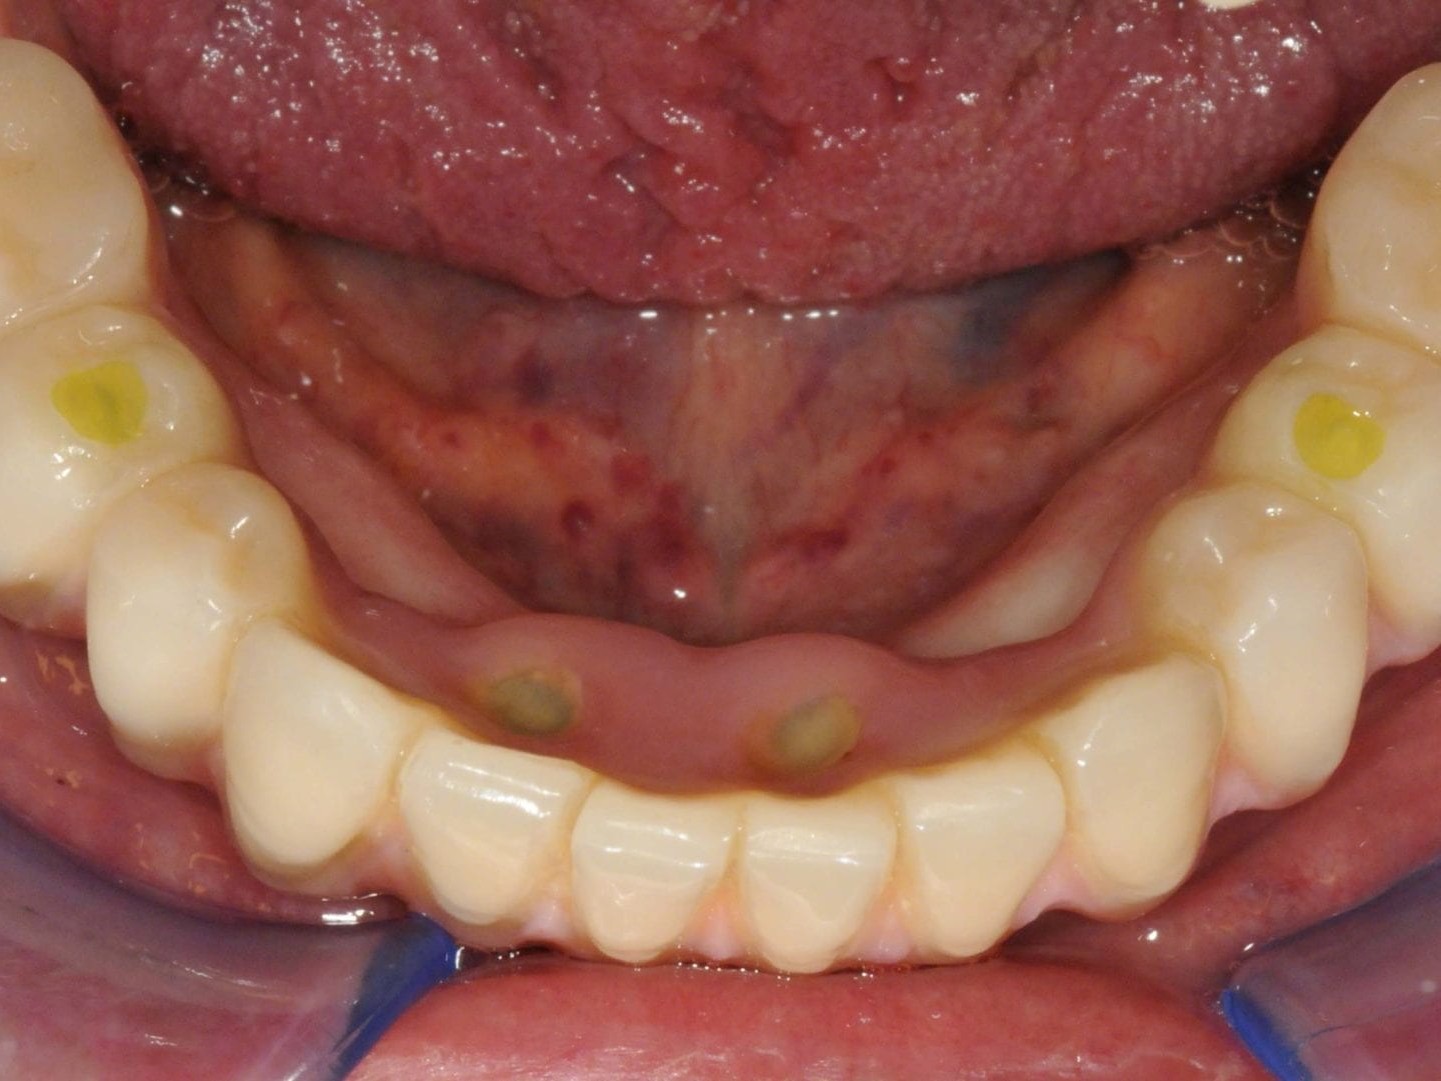

Wie weiter oben bereits beschrieben ist die Patientin im Oberkiefer mit einer keramisch verblendeten implantatgetragenen Brücke versorgt. Aus Sicht des Behandlungsteams schied daher eine keramische Verblendung des Unterkiefers aus. Die Verwendung von einem Composite mit keramischer Füllstruktur gewährleistet neben der notwendigen Farbstabilität und Plaqueresistenz zwei weitere Vorteile. Auf der einen Seite entsteht im Okklusionsmoment nicht das „keramische Klacken“ und zum anderen werden die auftretenden Kaukräfte gleichmäßiger auf das Implantat und den Knochen verteilt . Gerade bei implantologischen Oberkiefer- und Unterkieferversorgungen ist dieser „Stoßdämpfer–Effekt“ für den Langzeiterfolg wichtig. In dem vorliegenden Fall wurde die okklusal verschraubte Brücke aus einem massiven Titanblock gefräst (Abb. 4 und 5), wodurch das Endprodukt frei von aus der Gusstechnik bekannten Lunkern oder Verzügen ist. In Übereinstimmung mit den als Sheffield-Test ⁷ bekannten Kriterien der University of Sheffield, GB. ermöglicht dieser Fertigungsprozess gepaart mit der verblockten Abdrucknahme einen präzisen und somit spannungsfreien Sitz der Brücke – sowohl auf dem Meistermodell als auch im Munde des Patienten. Sowohl die Verblendungen der Zähne als auch des Zahnfleisches wurden unter Zuhilfenahme der diagnostischen Aufstellung mit visio.lign ⁸ im Labor angefertigt. Hierbei wurde besonderer Wert auf die naturgetreue Nachbildung der Rot-Weiß-Ästhetik und eine gute Hygienefähigkeit gelegt. Die Vorteile dieses Verblendsystems liegen in der exakten Umsetzung von der Aufstellung hin zur fertigen Arbeit durch mehrschichtige Verblendschalen (Abb. 6). Diese Verblendschalen werden schon bei der diagnostischen Aufstellung individualisiert und nach der Gerüstfertigstellung weiterverarbeitet. Mit passenden Individualisierungs- und Ergänzungsmassen sowie einem farblich abgestimmten Verbundsystem mit sehr guter Druck-Scheer-Festigkeit ⁹ ermöglicht dieses System durch Hinterlegen mit Intensivfarben das Gestalten von Mamelons ebenso wie die individuelle Gestaltung von Dentinleisten. (Abb. 7 und 8). Nach der zahntechnischen Erstellung der Unterkieferbrücke wurde diese intraoral inkorporiert (Abb. 9a). Die Implantatschrauben wurden mit 25 Ncm angezogen. Ein wichtiger Hinweis ist, dass hier stets das Originalequipment des Herstellers oder ein elektronisch kalibrierter Schraubendreher seine Anwendung finden sollte. Die Schraubenkamine wurden initial mit einem bakteriendichten, formstabilen lichthärtenden temporären Füllungsmaterial ¹⁰ verschlossen (Abb. 9b). Nach 6 Wochen werden die Implantatschrauben seitens des Prothetikers nochmals kontrolliert und ein abschließendes OPG erstellt (Abb. 10).